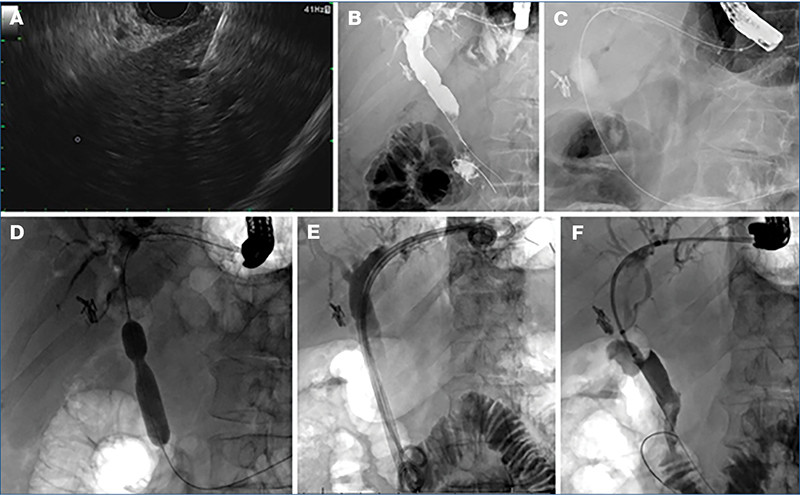

Az EUS-BD módszereinek ismertetése (1. ábra)

B: EUH-vezérelt antegrád stentelés, C: EUS-CDS, D: EUH-vezérelt cholecystadrenázs, E: EDGE, F: EUS-HGS (forrás: ESGE 2022 guideline) (34)

EUH-vezérelt randevútechnika (EUS-RV) és antegrád stentelés (EUS-HGAS)

Sikertelen ERCP után, könnyen elérhető papilla esetén választható opció az EUH-vezérelt randevútechnika. A sikertelen kanülálást ezen esetben egy, a szűkület feletti proximalisabb epeút pungálásával, majd distalis irányban a papillán átvezetett vezetődrót segítségével hidalhatjuk át. Ezután ERCP során fejezzük be az eljárást (pl. EST és kőeltávolítás, szűkületek stentelése stb.). Ez perkután bevezetett vezetődróttal is megoldható, az EUH-vezérelt megoldás választása a lokális ellátóhely tapasztalatától is függ.

Az antegrád stentelési eljárások megváltozott anatómia (pl. Roux-Y, Billroth II) vagy nyombélszűkület miatt nem elérhető papilla esetén jönnek szóba. Ilyenkor a gyomor felől egy bal lebenyi epeszegmensen keresztül juttatjuk a vezetődrótot a duodenumba, majd ezt követő tágítás után fém- vagy plasztikstentet helyezünk a distalis epeutak irányába. 2024-es metaanalízisben az EUS-HGAS 94%-os technikai és 89%-os klinikai sikerről számoltak be antegrád stentelés esetén 295 betegnél (13).

EUS-CDS (EUH-vezérelt choledochoduodenostomia)

Az eljárás olyan esetekben alkalmazható, amelyeknél a bulbus az eszköz számára biztonságosan elérhető, és az epe elvezetése megoldott a vékonybél distalis irányába (GEA, átjárható duodenum). Ezen eljárás alkalmával a bulbusból „hosszú úton” pungáljuk a közös epevezetéket a lézió felett és a hilus alatt ideálisan 3-4 cm-rel. Itt alkalmazhatunk lumenösszetartó fémstentet (LAMS), illetve vezetődrót mentén 6 Fr-es cystotommal átégetve a nyombél és az epeút falát 6 cm-es fedett SEMS-et (4. ábra). Alkalmazható randevútechnika ezen pozícióból is, de ekkor „rövid úton” a papilla irányába állunk az eszközzel. Az EUS-CDS-t vizsgáló 2024-es metaanalízis (845 beteg) a technikai és klinikai sikerességet 96%-osnak találta. A nemkívánatos események aránya 12% volt. Itt a 8×8 mm-es LAMS jobb volt a nemkívánatos események terén, mint a 6×8 mm-es (19).

EUH-vezérelt transgastricus ERCP (EDGE)

Tekintve, hogy ezen eljárás során nem direkt az epeutakat drenáljuk, csak érintőleges leírást adunk az eljárás lehetőségéről. Gyomorbypass után első lépésben LAMS segítségével a kirekesztett gyomorrészt szájaztatjuk a megmaradt proximalis gyomorcsonkhoz, majd duodenoszkópra váltva, az eredeti anatómiát követve hajtjuk végre a hagyományos ERCP-t. Alternatívája lehet malignus eltérés esetén az antegrád stentelés (1. ábra).